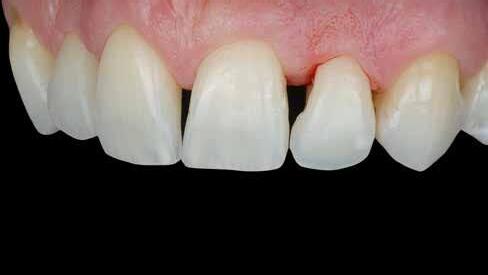

Egy 30 éves, negatív kórtörténettel rendelkező beteg azzal a kéréssel fordult hozzánk, hogy cseréljük ki az UR1 traumája után, 10 évvel korábban készült korábbi kompozit-helyreállítást.

A klinikai vizsgálat során az UR1 reagál a viabilitási tesztre, és az ugyanazon a napon készült röntgenfelvételen nem mutat periapikális elváltozásokat (1. ábra).

Az UR1 elszíneződött, és palatálisabb helyzetben van, mint az ellenoldali központi UL1 (2. ábra)

Az esztétikai elemzés a gingivális zenit aszimmetriáját mutatja az UR1 és az UL1 között. Parodontális szonda segítségével, plexusérzéstelenítés után, az IA

típusú funkcionális hám megváltozott passzív erupcióját igazoljuk Coslet és mtsai. osztályozása szerint (3. ábra)

A lehető legkonzervatívabb helyreállító kezelés elvégzése érdekében a páciensnél, figyelembe véve a megtartott fogelem korát és vitalitását, a tervezés és a diagnosztikai felviaszolás után a közvetlen kompozit-helyreállítás elvégzése mellett döntünk.

A kezelés napján, helyi plexusérzéstelenítést követően, az UR1-et kofferdámmal izoláljuk, kiterjesztve az izolációt az első premolárisokra (4. ábra)

Ezt követően eltávolítjuk a törött kompozt-helyreállítást, és az előkészített fogon rövid ferdére preparálást készítünk, majd az UR1 teljes felületén homokfúvást végzünk 27 μm-es alumínium-oxid porral (5. ábra)

A megváltozott passzív erupció korrigálása érdekében úgy döntöttünk, hogy a fog kiemelkedési profilját a vesztibuláris kidomborodás hangsúlyozásával és az ellenoldali elemmel való szimmetriára törekvéssel újra létrehozzuk. Erre a célra

egy előre megformázott fémmatricát használunk, amelyet két ékkel blokkolunk.

A matrica adaptálása után az adhéziós eljárásokat egy 3 lépéses etch&rinse rendszerrel végezzük. Minden egyes lépést 40 másodperces, UV-fénnyel történő polimerizálás követ (6. ábra)

A vesztibuláris kiemelkedési profilt zománcszínű kompozittal (a TOKUYAMA DENTAL ESTELITE ASTERIA WE termékével) állítjuk helyre (7. ábra).

A diagnosztikai felviaszolás szilikonindexének elkészítése után a palatinális falat zománcszínű kompozittal (a TOKUYAMA DENTAL ESTELITE ASTERIA WE termékével) helyreállítjuk (8. ábra)

Ezt követően helyreállítjuk a dentin anatómiáját a mamelonok reprodukálásával egy átlátszatlan dentinszínű kompozittal (a TOKUYAMA DENTAL ESTELITE SIGMA QUICK OA2 termékével); ez a szín alapvető fontosságú lesz a diszkromatikus elem színének korrigálásához is (9. ábra) Világoskék és fehér hatású árnyalatokat (a TOKUYAMA

DENTAL ESTELITE COLOR termékét) alkalmazunk az opá-

losság emulálásához az incizális területen (10. ábra)

A rétegezést egy zománcszín (a TOKUYAMA DENTAL ESTELITE ASTERIA WE terméke) használatával végezzük a vesztibulárisban, egyszeri hozzáadással. A vesztibuláris felületet háromdimenziós térfogatban modellezzük és vezéreljük annak érdekében, hogy a lehető legkevesebb végső kiigazítás legyen. Ezután 20 másodpercig polimerizáljuk, majd 40 másodpercig polimerizáljuk vesztibulárisan és palatinálisan, miután bevontuk őket gliceringéllel a kompozit hibrid rétegének elkerülése érdekében (11. ábra).

A finírozási és polírozási eljárásokat úgy végezzük, hogy megpróbáljuk emulálni az UL1 átmenő vonalait (12–13. ábra)

A pácienst 21 nap (14–15. ábrák) és 12 hónap (16. ábra) után ismét ellenőrizzük, hogy értékeljük az esztétikai eredményt a forma és a szín tekintetében.